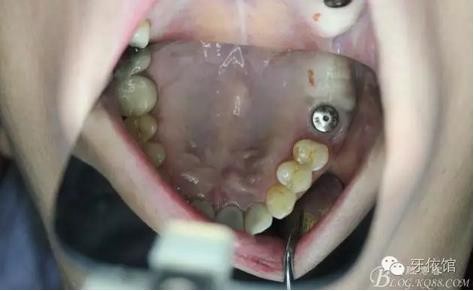

術(shù)后6個月口內(nèi)照

右上7上愈合基臺